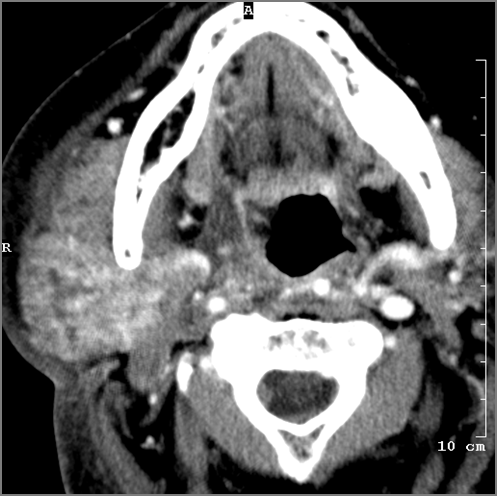

Oropharynx

There is edema/abscess tonsillar or otherwise or likely suppurative retropharyngeal adenitis involving the oropharynx or adjacent deep tissue spaces.

Major Salivary Glands

The parotid, submandibular and sublingual glands are enlarged.

The parotid, submandibular and sublingual glands do show abnormal enhancement.